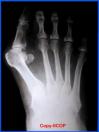

Hallux ValgusLa inflamación postquirúrgica del hallux valgus desaparece cuatro meses después de intervenirlo, según un estudio que ha medido la evolución de la hinchazón, una cuestión apenas estudiada y que ha publicado Carlos Piqué-Vidal en Foot and Ankle Surgery.

La inflamación postquirúrgica del hallux valgus, una cuestión apenas estudiada hasta ahora, desaparece cuatro meses después de su intervención, según un estudio publicado en la revista europea Foot and Ankle Surgery y realizado por Carlos Piqué-Vidal, del Centro Médico Teknon, de Barcelona.Anteriormente, los cirujanos vasculares utilizaban el método de inmersión, consistente en sumergir el miembro del paciente en agua y deducir su inflamación, en función del volumen de líquido que sube, pero no se practicaba en personas operadas, ha explicado Piqué-Vidal.

Su trabajo se ha centrado en evaluar la evolución clínica de la inflamación, midiendo cinco parámetros tras la cirugía del hallux valgus: el grosor y circunferencia del antepie, el grosor y circunferencia del primer dedo y la anchura del pie.El objetivo ha sido establecer una correlación entre el curso de la hinchazón postquirúrgica y la curación completa de los pacientes. "Poder decirles que la inflamación bajará nos ayuda a tranquilizarles y contribuye a su curación".

La medición de los parámetros se ha realizado con cinta métrica y pie de rey digital en una población de 146 pies de 85 pacientes operados por el procedimiento de Reverdin-Isham, con mínima incisión.Al comparar las medidas preoperatorias con las tomadas en las semanas 6 y 16 tras la cirugía se ha observado una evolución diferente de los distintos parámetros.